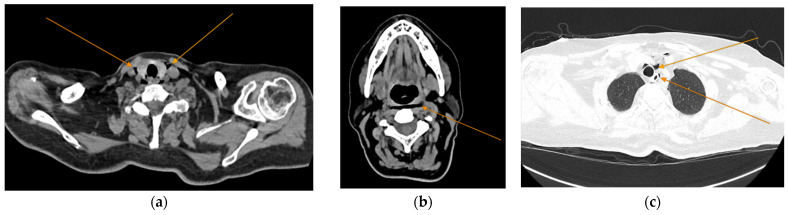

Background and Clinical Significance: Diabetic ketoacidosis (DKA) is a serious and potentially life-threatening condition, often triggered by infections or undiagnosed diabetes. Spontaneous pneumomediastinum (SPM) and pneumothorax are rare but recognized complications of DKA, possibly due to alveolar rupture from increased respiratory effort or vomiting. Sometimes, acute pancreatitis (AP) may further complicate DKA, but the co-occurrence of these three conditions remains exceptionally rare. Case Presentation: We describe the case of a 60-year-old woman without a known history of diabetes who arrived at the emergency department with abdominal pain, fatigue, vomiting, and altered mental status. Initial laboratory findings showed metabolic acidosis, hyperglycemia, and elevated anion gap, consistent with DKA. Imaging revealed spontaneous pneumomediastinum and subsequently a left-sided pneumothorax, without evidence of trauma or esophageal rupture. Epigastric pain, along with elevated serum lipase and CT findings, also confirmed acute pancreatitis. Despite the complexity of her condition, the patient responded well to supportive treatment, including oxygen therapy, fluid resuscitation, insulin infusion, and antibiotics. She was discharged in good condition after 28 days, with a confirmed diagnosis of type 2 diabetes, without further complications. Conclusions: This case highlights an unusual combination of DKA complicated by spontaneous pneumomediastinum, pneumothorax and acute pancreatitis in a previously undiagnosed diabetic patient. Because prompt intervention can lead to favorable outcomes even in complex, multisystem cases, early recognition of atypical DKA complications is critical in order to avoid misdiagnosis.